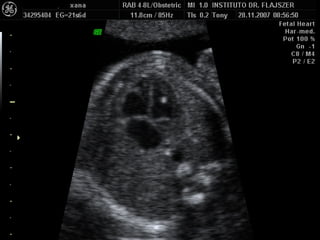

ECOCARDIOGRAFIA FETAL Modo B Modo M Doppler ¿CUANDO? A partir de la sem 12 por vía TV A partir de la sem 18 por vía abdominal Optimo: semana 22

Evaluación del corazón fetal en la ecografía obstétrica Modo B ¿CUANDO? Segundo y tercer trimestres ¿Como? De mayor a menor

EXAMEN BASICO GENERAL Ubicación Eje Tamaño  Cámaras Pericardio Ritmo VALVULAS AV Apertura y movimiento Inserción AURICULAS Tamaños Flap del foramen oval Septum VENTRICULOS Tamaños Paredes Banda moderadora Tabique

EXAMEN BASICO GENERAL Ubicación Eje Tamaño  Cámaras Pericardio Ritmo